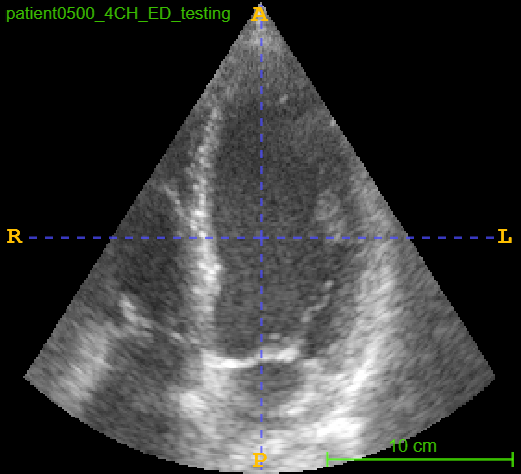

4.3 CAMUS Echocardiogram View Classification

After investigating the issue of synthetic simplicity in the digit classification task, we demonstrate the phenomenon on a representative medical imaging task of cardiac view classification from echocardiographs. We utilized the publicly available echocardiography dataset "Cardiac Acquisitions for Multi-structure Ultrasound Segmentation" (CAMUS) [8] for this experiment. The CAMUS dataset comprises four types of cardiac views from over 500 subjects: two-chamber end-systolic (2CH ES), two-chamber end-diastolic (2CH ED), four-chamber end-systolic (4CH ES), and four-chamber end-diastolic (4CH ED). We focused on the "4CH ED" and "2CH ED" classes in the CAMUS dataset for classification task. Figure 2 shows real and synthetic samples of 4CH ED and 2CH ED echocardiogram views.